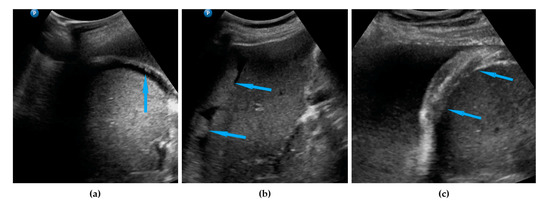

| Peritoneum, abdomen | Abdomen carcinomatosis manifest as hypoechogenic lesions over the peritoneal surface of the paracollic gutters or internal abdominal wall. | Figure 3 | Video S3 |

| Peritoneum, pelvis | Pelvic carcinomatosis manifests as hypoechogenic lesions over the peritoneal surface of the pelvic wall: laterally, in the pouch of Douglas (no rectum involvement) or the bladder in the uterine serosa. | Figure 4 | Video S4 |